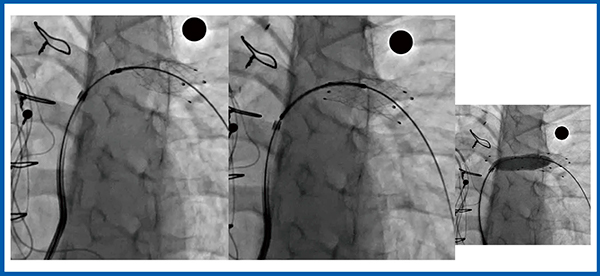

図2は,経皮的心房中隔欠損閉鎖術(Amplatzer Septal Occluder:ASO治療)におけるwiggleによるデバイスの安定性の確認の様子であるが,デバイス強調モード(b)ではきわめて明瞭に描出されている。

図2 デバイス強調モード:ASO治療

図3は,経皮的動脈管開存閉鎖術(Amplatzer Duct Occluder:ADO治療)であるが,デバイス強調モード(b)では,デバイスやシースはもとより,気管支透亮像との位置関係もわかりやすい。

図3 デバイス強調モード:ADO治療